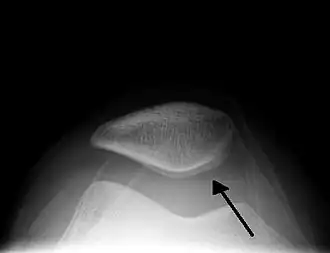

| Traumatic effusion of the right knee, with swelling lateral to the kneecap marked by an arrow | |

X-Ray

An X-ray may be recommended by your provider as a way to obtain a 2-dimensional image to visualize the joint in question. In the presence of trauma an X-ray can be especially useful to verify that there is no break, dislocation, or deformity. In an atraumatic knee, an X-Ray can be used to identify or rule out other causes of a knee infusion including some inflammatory or age-related causes.